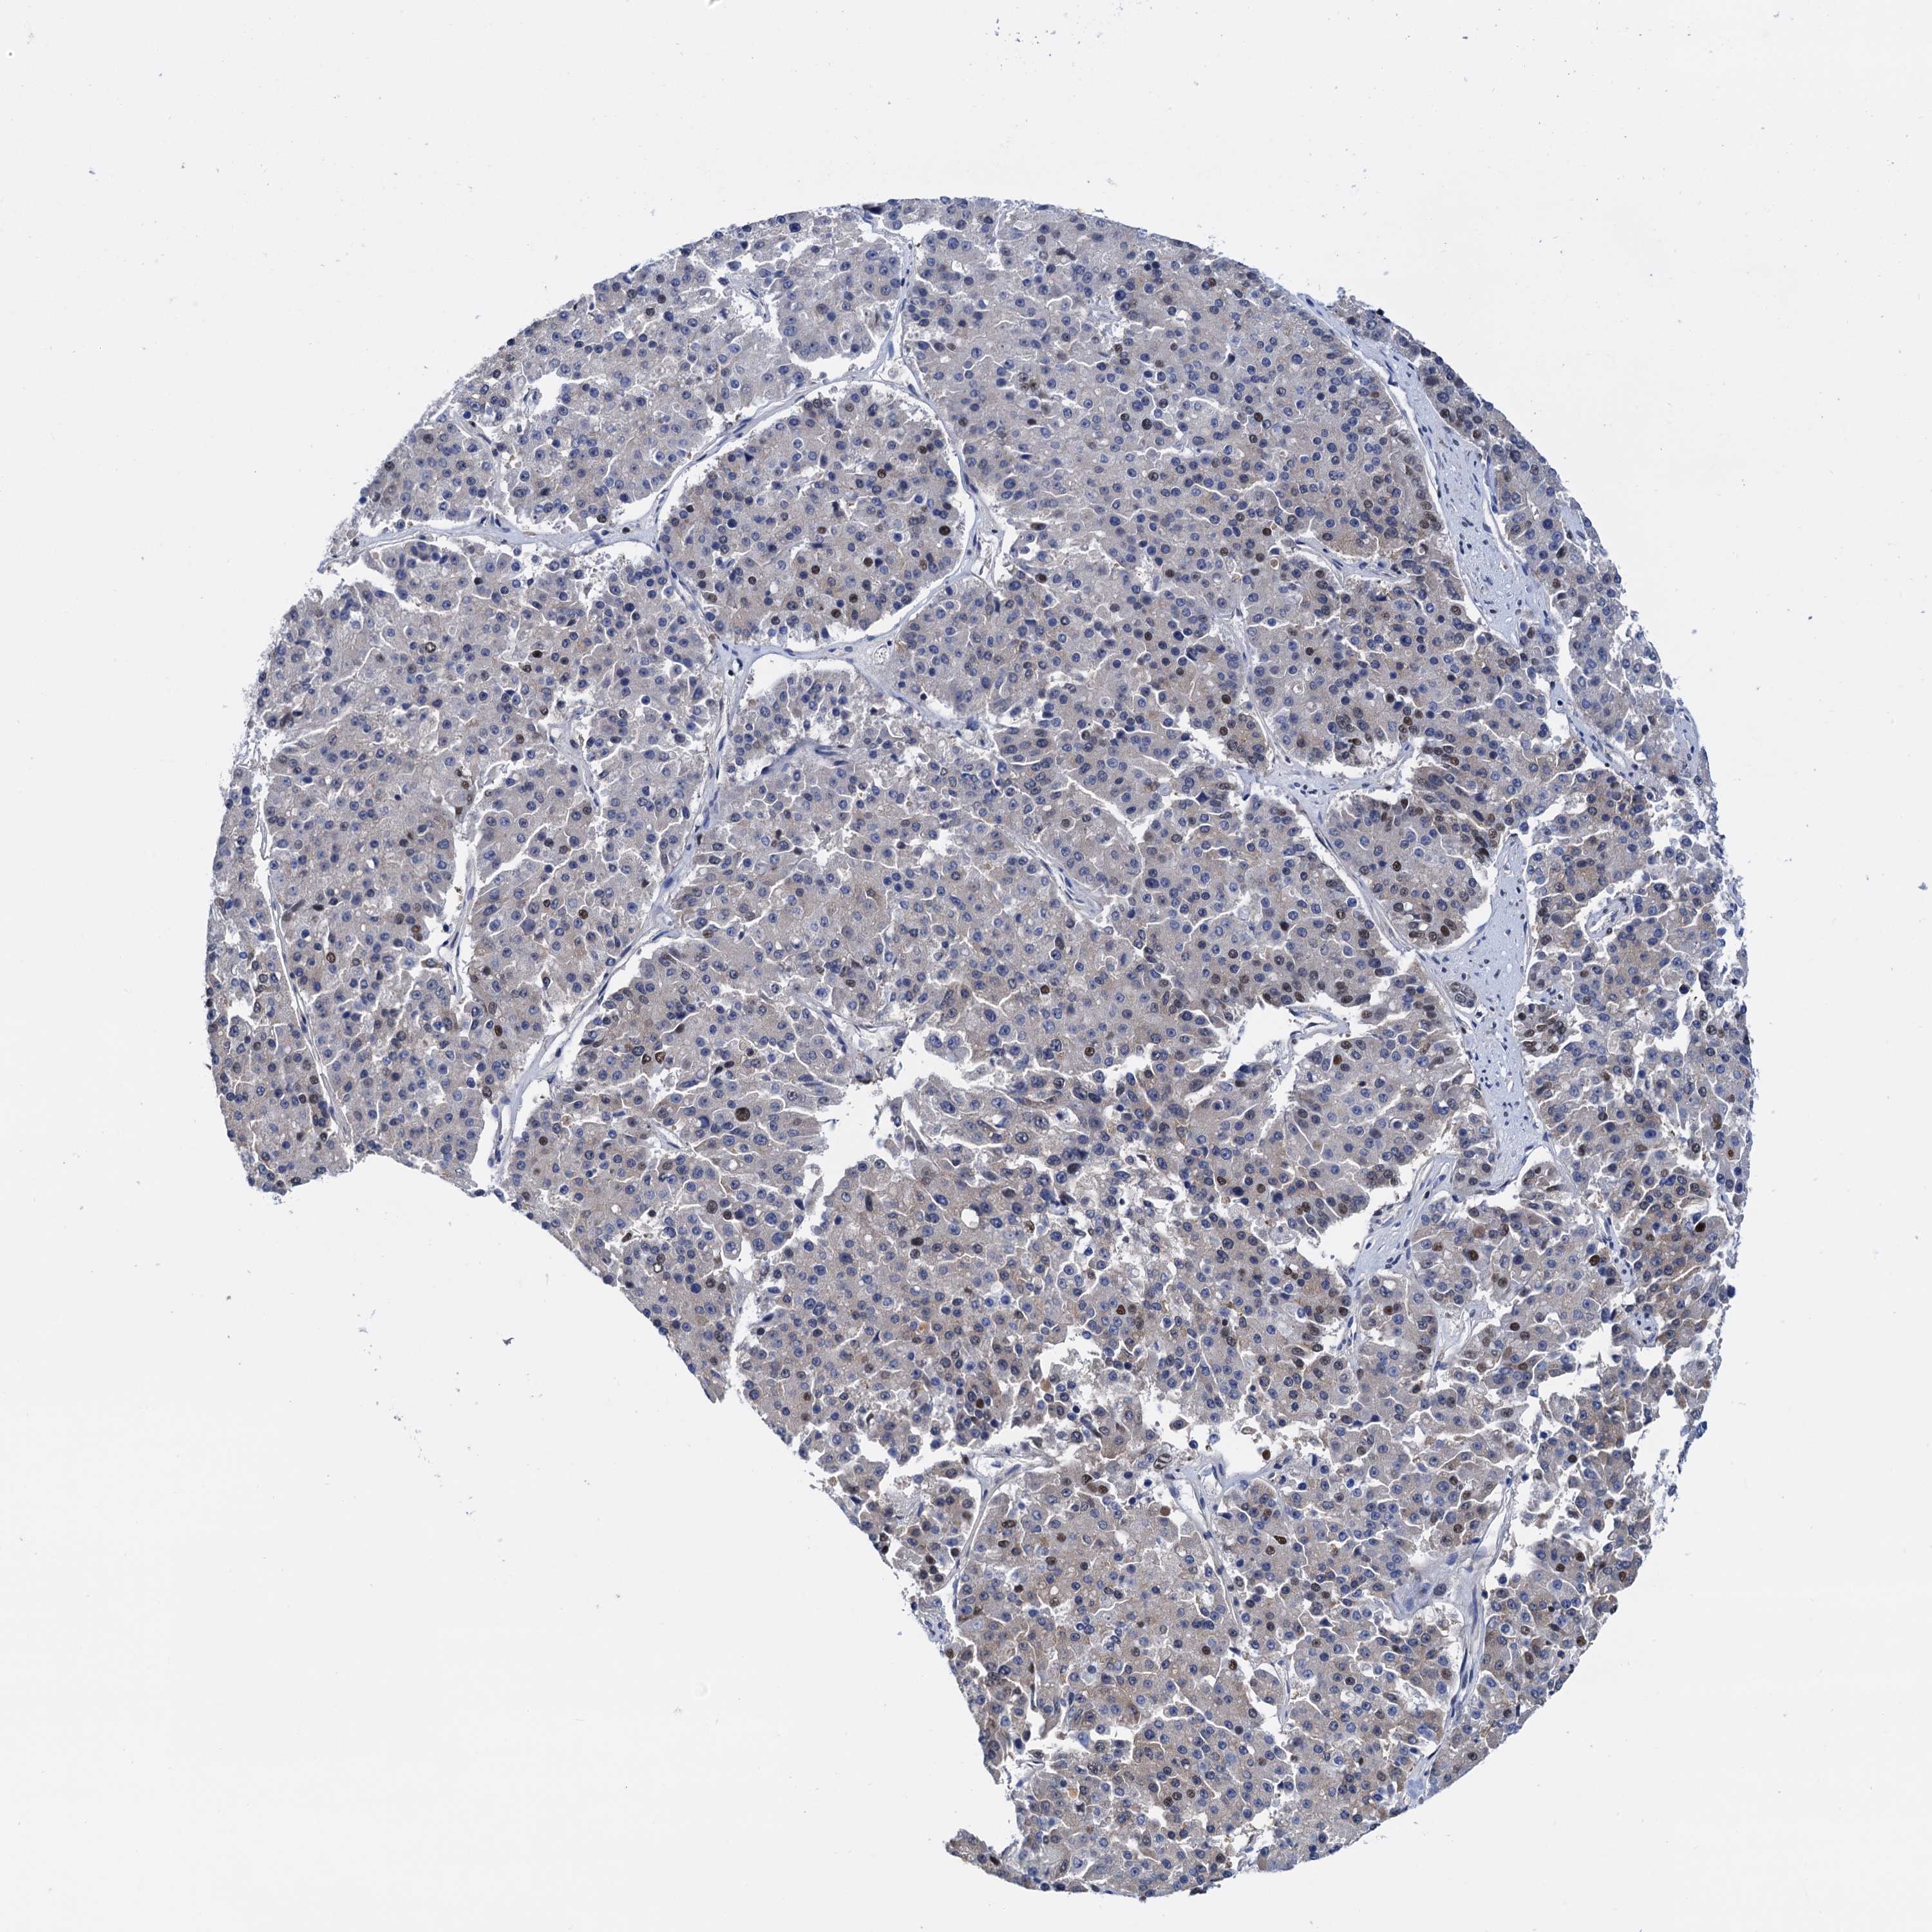

PANCREATIC CANCER - Protein expressioni

A mouse-over function shows sample information and annotation data. Click on an image to view it in a full screen mode. Samples can be filtered based on level of antibody staining by selecting one or several of the following categories: high, medium, low and not detected. The assay and annotation is described here.

Note that samples used for immunohistochemistry by the Human Protein Atlas do not correspond to samples in the TCGA dataset.

Antibody stainingi

Antibody staining in the annotated cell types in the current human tissue is reported as not detected, low, medium, or high, based on conventional immunohistochemistry profiling in selected tissues. This score is based on the combination of the staining intensity and fraction of stained cells.

Each image is clickable and will lead to virtual microscopy that enables deeper exploration of all samples and also displays staining intensity scores, fraction scores and subcellular localization as well as patient and tissue information for each sample.

Antibody HPA040256

Antibody HPA040381

Staining

High

Medium

Low

Not detected

Intensity

Strong

Moderate

Weak

Negative

Quantity

>75%

75%-25%

<25%

None

Location

Nuclear

Cytoplasmic/membranous

Cytoplasmic/membranous,nuclear

Adenocarcinoma, NOS